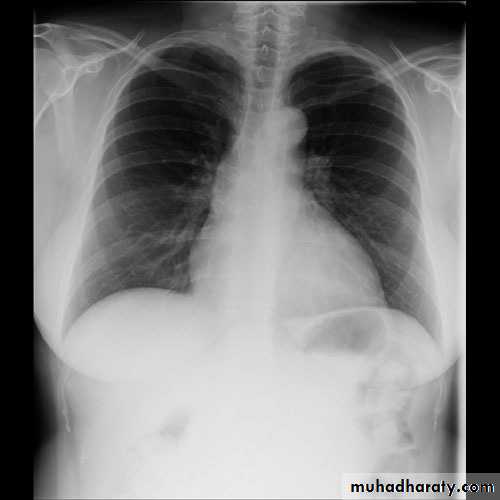

1- Perforation